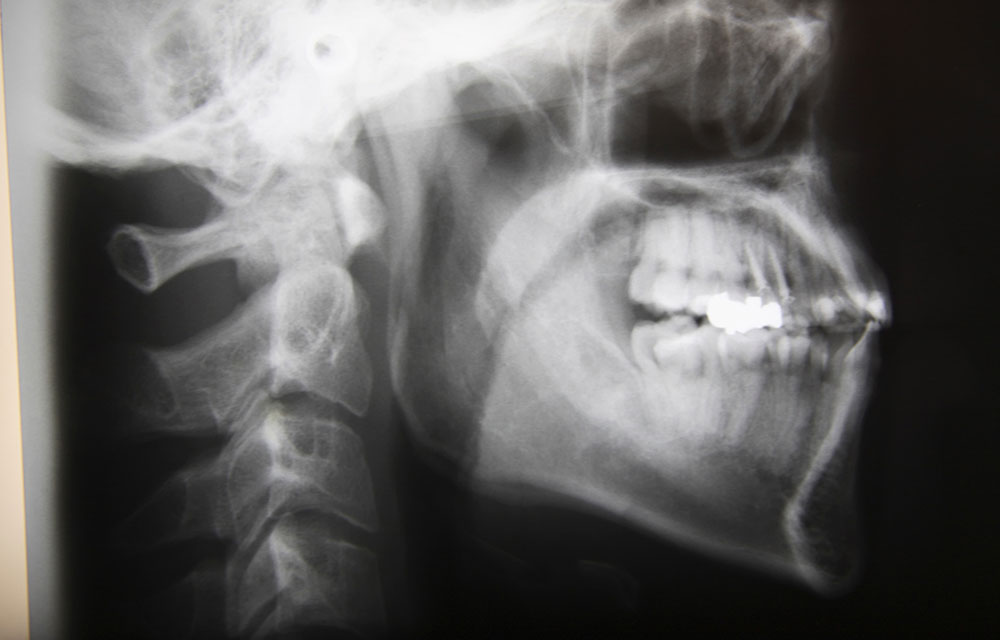

セファログラムによる分析

矯正治療を行う際には歯だけではなく、顔全体の骨格を分析するためにセファログラムというレントゲン写真を撮影します。そこから導き出される数値を元に分析し矯正治療の治療計画を立てます。分析結果によって治療の際に抜歯の有無も判断します。

また、レントゲン写真だけでなく、模型から計算して導き出される数値も重要な判断基準となります。